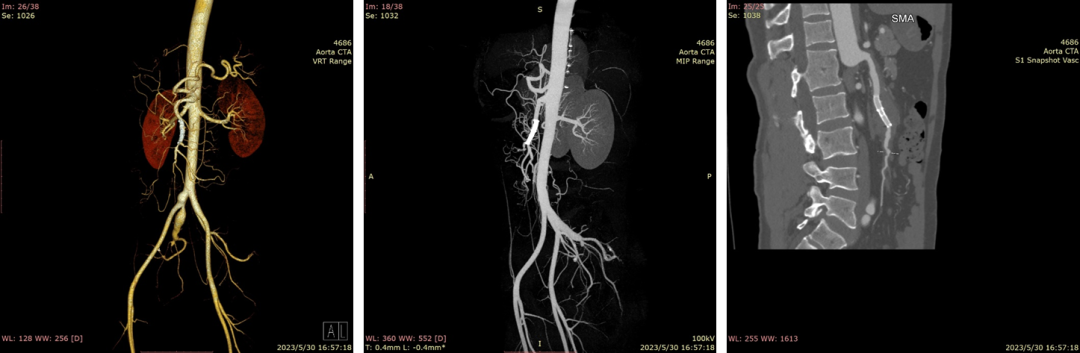

20230530CTA(术后1周):夹层动脉瘤隔绝完全